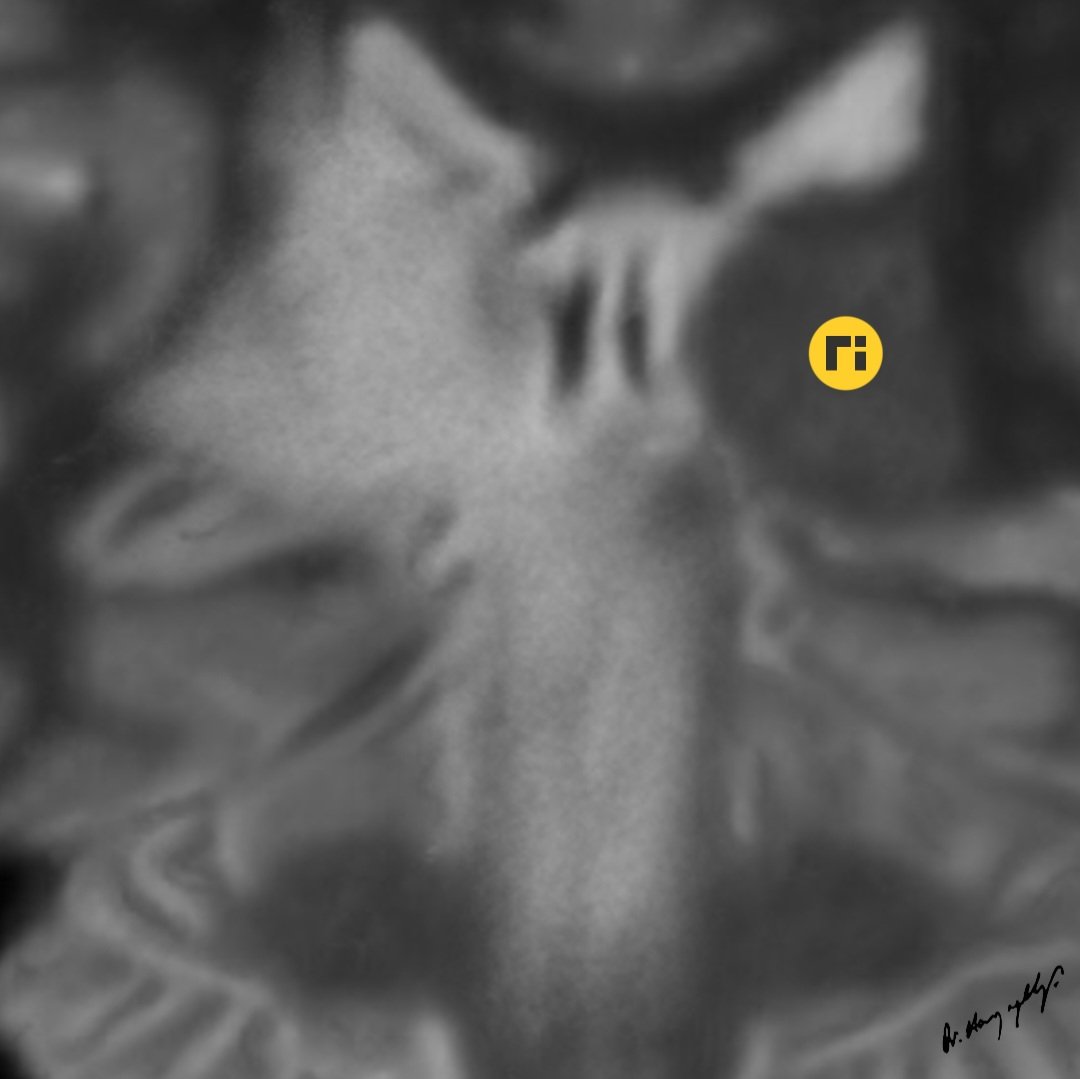

“Waterfall Sign" / Neuro-Behçet doi.org/10.1016/j.radc… ajnr.org/content/quiz/1… #radiologicalillustration ✍️ Pixel by Pixel Handmade!

drharunyildiz's tweet image. “Waterfall Sign" / Neuro-Behçet